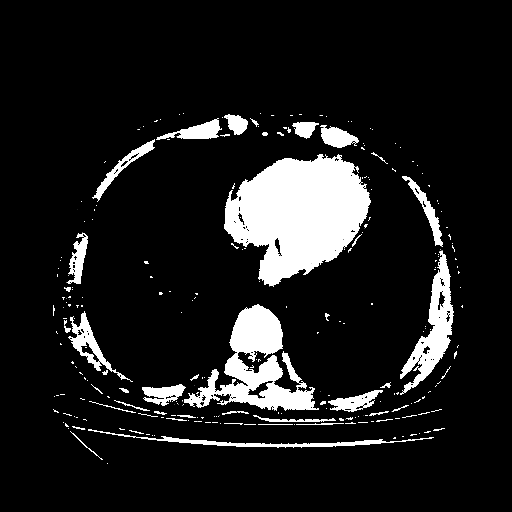

Generated VENOUS CT scan (A→B translation)

Full window (WL 1023.5, WW 4095 β†’ Low βˆ’1024, High +3071)

Actual HU range: [-1024.0, 3071.0]